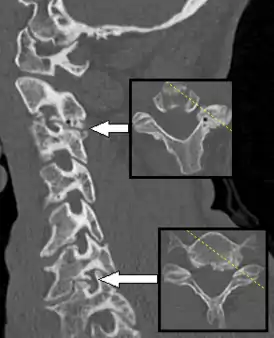

При спондилёзе костная ткань суставов разрастается, образуются остеофиты, то есть дополнительная костная ткань (по мере нарастания костный вырост распространяется к соседнему позвонку, тогда как от соседнего позвонка образуется такой же вырост, в некоторых случаях окостенение начинается на уровне межпозвоночного диска). В особо тяжелых случаях наступает сращение позвонков, от чего страдают сосуды, нервы и мышечная ткань, а также близлежащие органы.